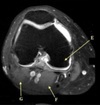

INFRASPINATUS MUSCLE

10

Q

What is letter D?

A

GLENOID

How well did you know this?

1

Not at all

2

3

4

5

Perfectly